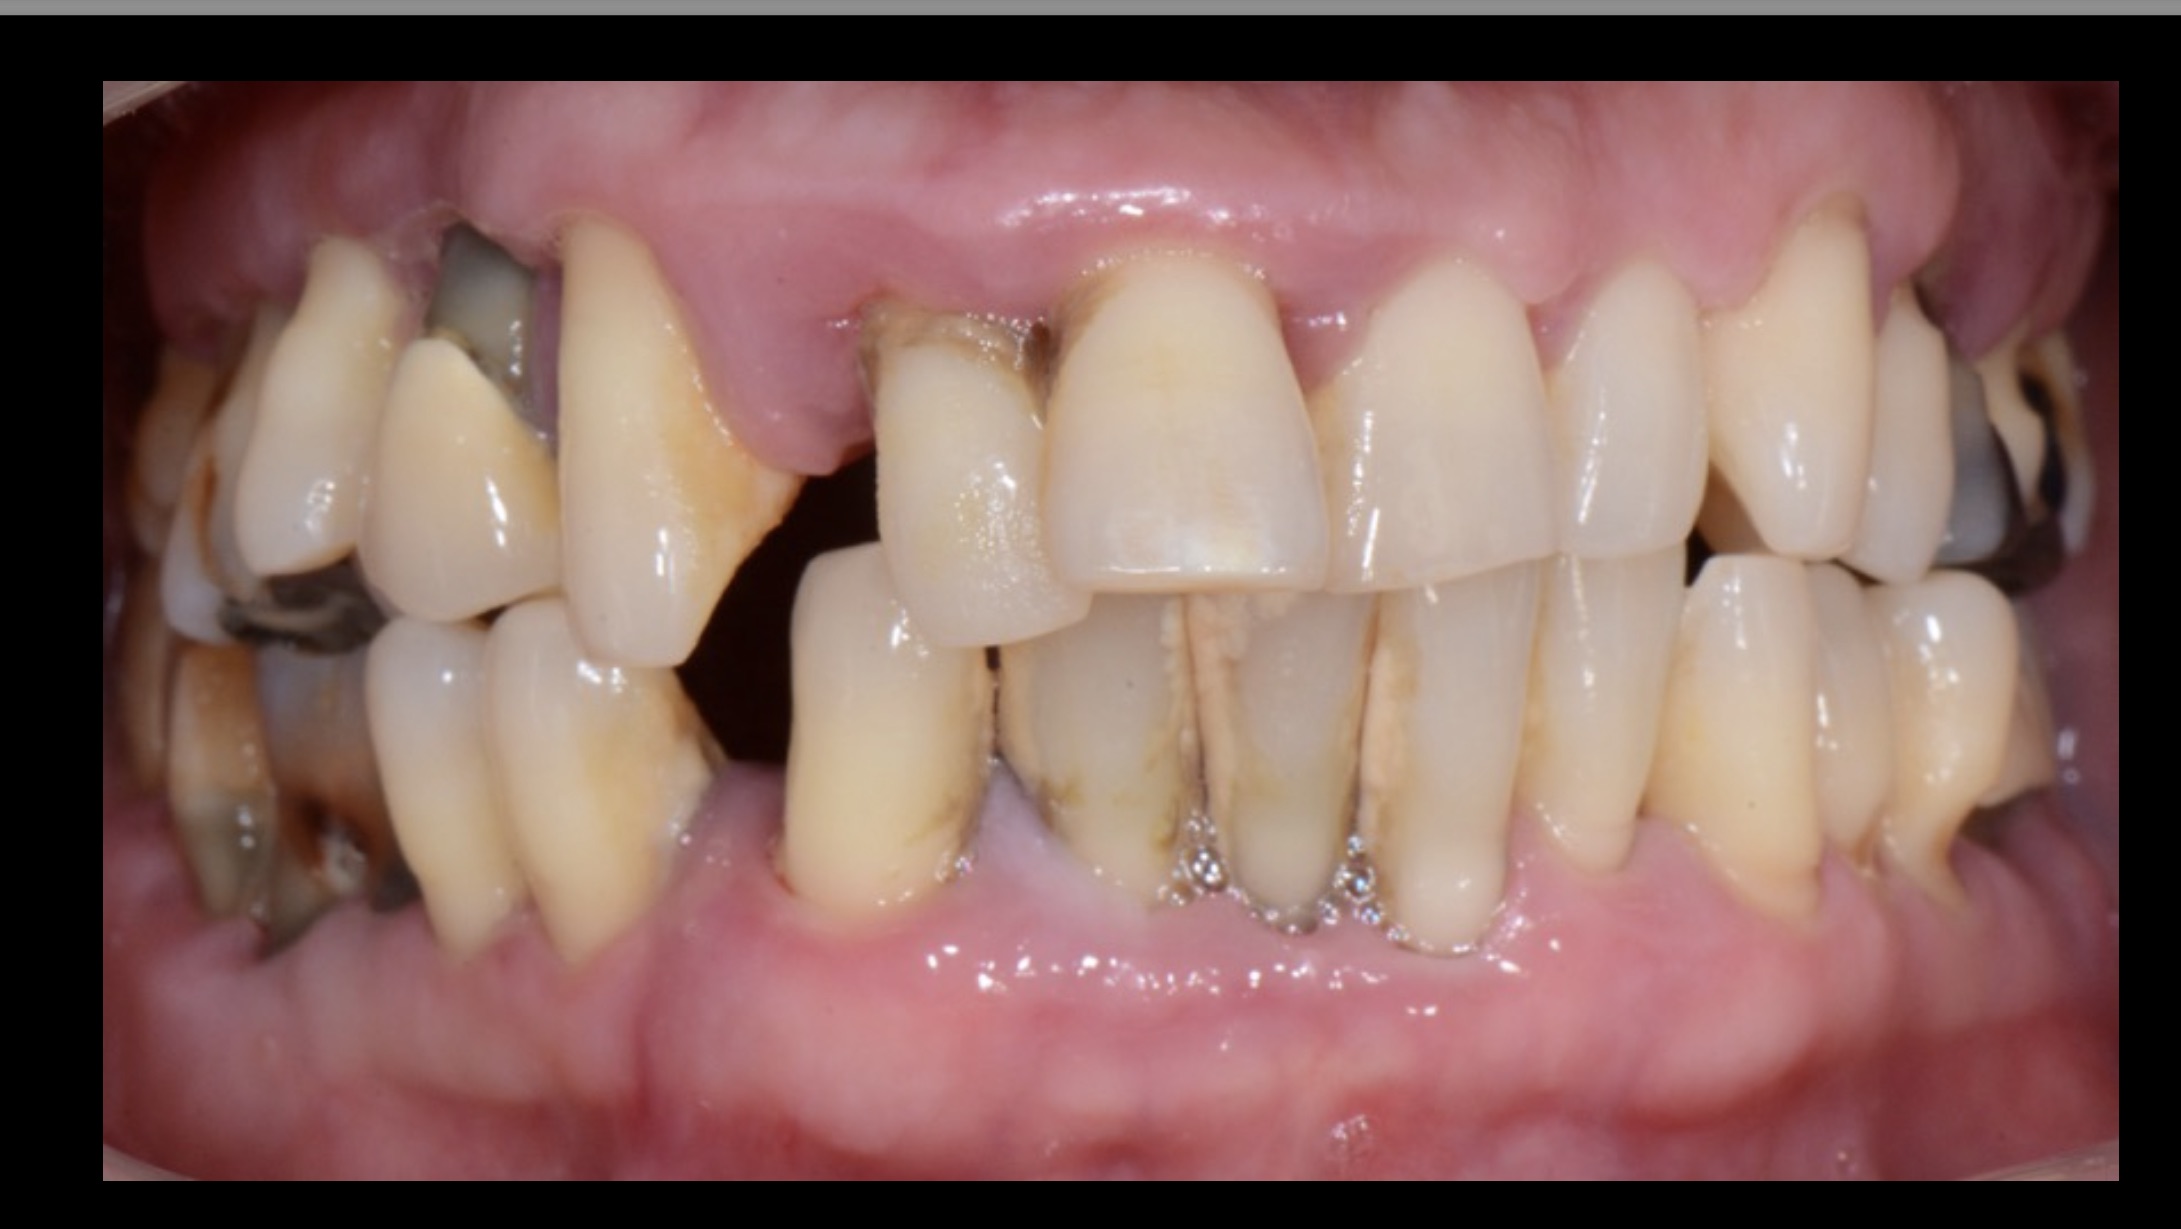

גלריית הצגת מקרים לפני ואחרי